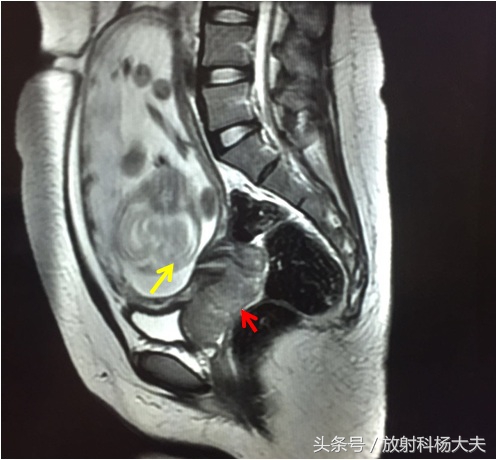

两年前遇到一个病例,女性,23岁,孕20周+4天,因阴道流血来医院检查,小两口很紧张,以为是孩子出了什么问题,做了超声,结果是宫颈占位,所以临床大夫又给患者开了核磁申请单,大家可能会想,不是超声已经确诊是宫颈占位了么,为什么还要做核磁(MRI)。对于宫颈病变,MRI可以说是最好的检查方法,可以直接的观察肿瘤的大小,观察阴道及宫旁侵犯,观察盆腔内淋巴结及对病变进行分期。先给大家上图:

红箭所指的地方就是病变,还可以看见肚子里的宝宝(黄箭)。而且经过进一步的分析,病变已经累及阴道及直肠,提示为宫颈癌的晚期!

对于局部病变的显示,MRI无疑是最好的。因此临床上进行术前分期的时候都选择MRI检查。宫颈基质的低信号环是否完整是宫颈癌I期与II期的分界标志,完整的低信号环说明癌灶局限在宫颈,可排除有宫旁组织的侵犯。如低信号的基质环被高信号的肿瘤破坏,出现中断或是突破,提示肿瘤已经侵犯宫旁组织,属于II期。肿瘤累及阴道下1/3、盆腔、直肠等周围脏器,为III 、IV期。